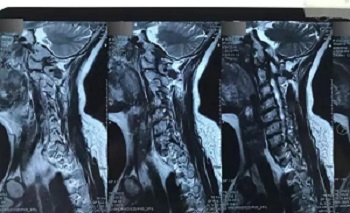

十一、将分区的磁共振图像,按顺序进行拍摄,即可获取如下比较有价值的清晰图片

(区域1)

(区域2)

(区域3)

(区域4)

(区域5)

(区域6)

(区域7)

(区域8)